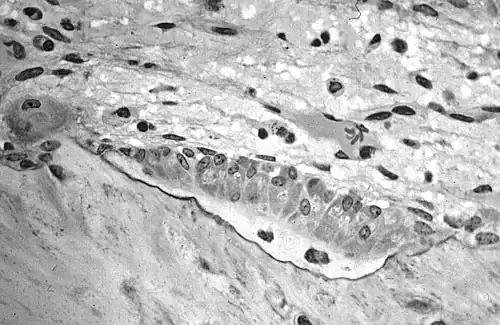

Afbeelding met meerdere osteoblasten. In de TEM-afbeelding kan de door de osteoblasten gesynthetiseerde osteoïd duidelijk worden gezien als een heldere zone (zwarte grenslijn) met twee ingebedde osteocyten, scherp afgebakend in de richting van de gemineraliseerde botmatrix.

Osteoïd[1] of botmatrix[1] is een eiwitmengsel dat uitgescheiden wordt door osteoblasten. Als het mineraliseert, wordt het botweefsel. Het mengsel bevat vooral type 1-collageen, daarnaast ook glycosaminoglycanen en proteoglycanen.